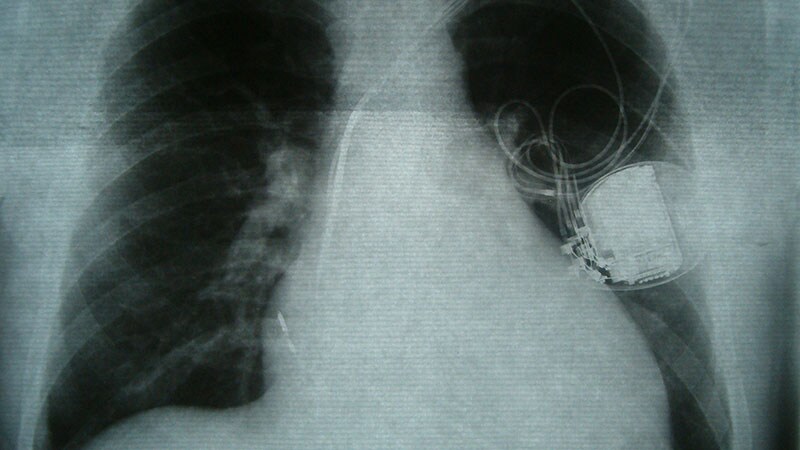

EHRA 2023High-Power Electric Car Chargers Safe With Cardiac DevicesHigh power chargers for electric vehicles were safe for use by patients with cardiac implantable electrical devices, according to the results of a study testing a variety of chargers and devices.